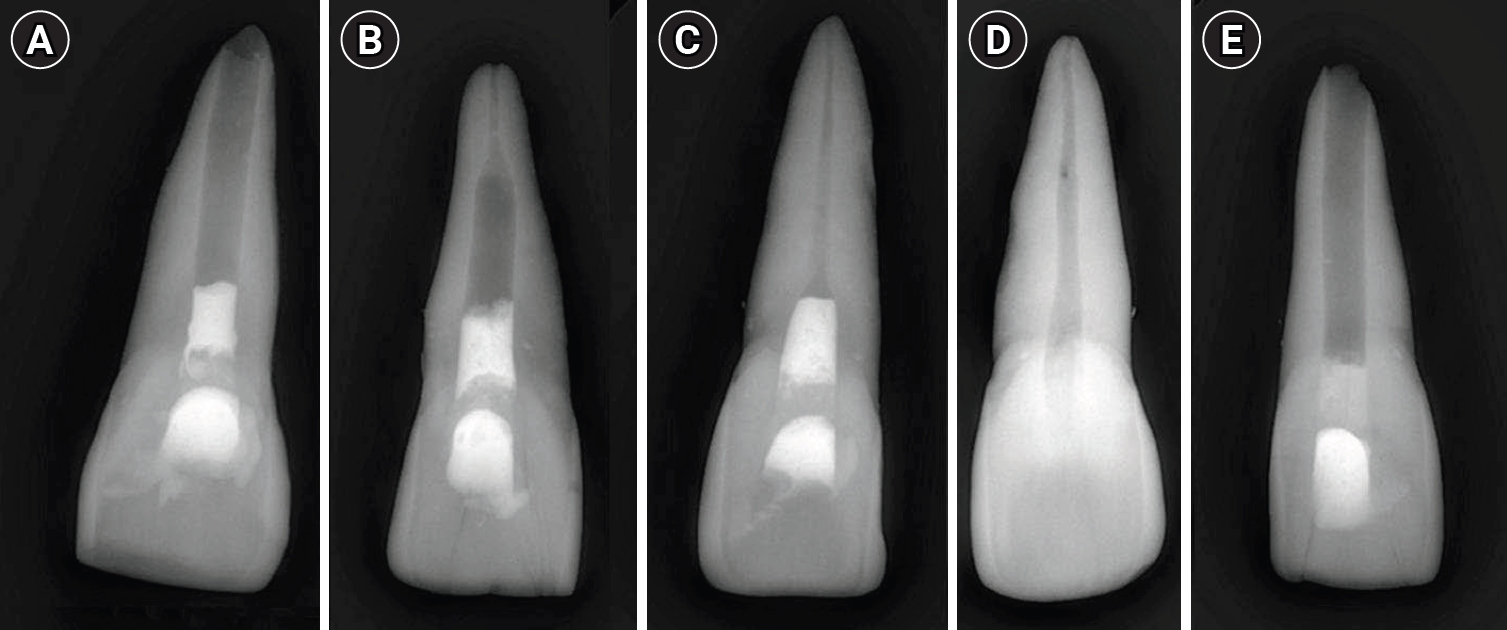

Simulation of immature teeth

Experimental groups were instrumented in order to represent three different stages of root development: completely immature teeth (Group A), teeth with apical closure (Group B), and teeth with apical closure and wall thickening (Group C). Intact teeth served as negative controls (Group D), while teeth with simulated immature roots without material placement served as positive controls (Group E) (Figure 1). The completely immature groups were classified as stage 3 according to Cvek’s classification [14].

Figure 1.

Representative radiographic images of the five study groups. (A) Completely immature teeth immediately after treatment (Group A). (B) Teeth with apical closure (Group B). (C) Teeth with apical closure and wall thickening (Group C). (D) Intact teeth (negative control, Group D). (E) Simulated immature teeth without material placement (positive control, Group E).